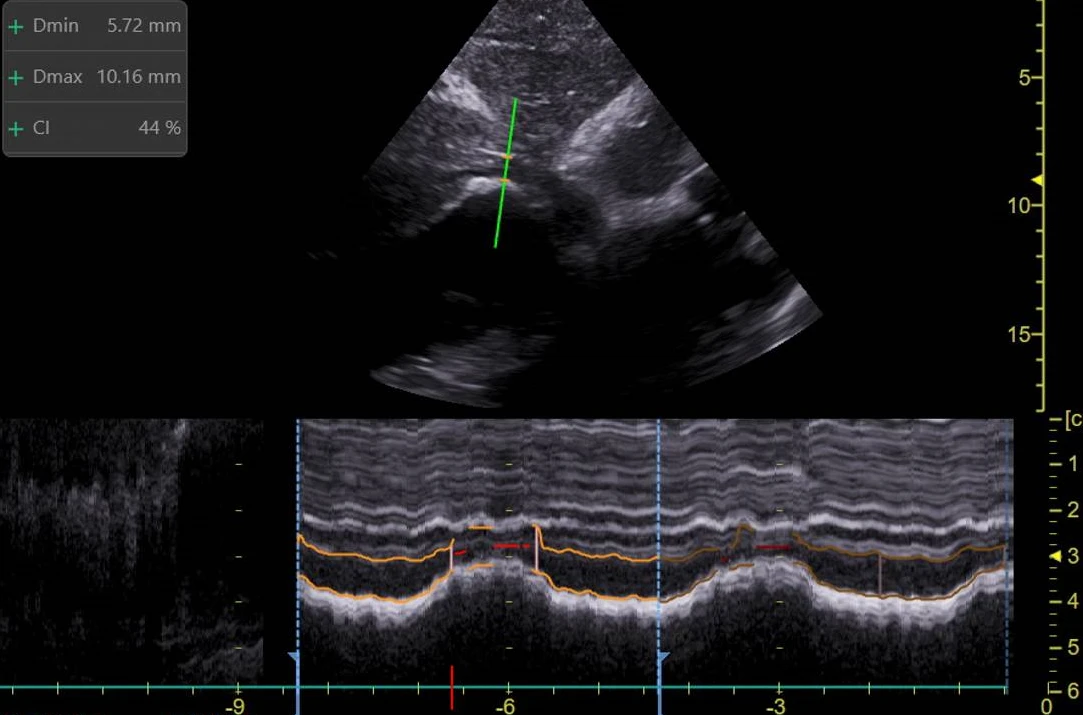

La mesure du diamètre de la veine cave inférieure (VCI) et sa variabilité respiratoire est utilisé pour estimer le volume intravasculaire d’un·e patient·e. Dans l’état de choc, cette estimation aide la ou le clinicien·ne à prédire la réponse au remplissage.

Comme il n’y pas de valve entre la VCI et l’oreillette droite, le diamètre et la variation du diamètre de la VCI est parfois considérée comme un reflet de la pression dans l’oreillette droite (POD). La variation respiratoire de la VCI est aussi appelée index de collapsus ou index cave (CI sur l'image). Il est exprimé en pourcent et obtenu en divisant le plus petit diamètre par le plus grand. Chez la ou le patient·e qui respire spontanément, le diamètre de la VCI diminue à l’inspirium à cause de l’augmentation du volume thoracique qui réduit la pression intra-thoracique. Au contraire, chez la personne ventilée mécaniquement, la pression intra-thoracique augmente en phase d’inspiration, faisant augmenter le diamètre de la VCI à quelques centimètres de son arrivée dans l’OD.

La veine cave inférieur est mesurée dans son axe longitudinal, le plus souvent en sous-xyphoïdien. Le diamètre devrait être mesuré à environ 2cm (ou plus) de l’OD. Le mode M permet de mesurer facilement la variabilité respiratoire de la VCI.

Image proposée par Perrine Truong, CHUV.